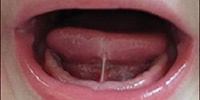

Tongue Tie Assessment and Evaluation for the Chiropractor

This webinar is designed to assist Doctors of Chiropractic assess and evaluate tongue tie in the infant population.